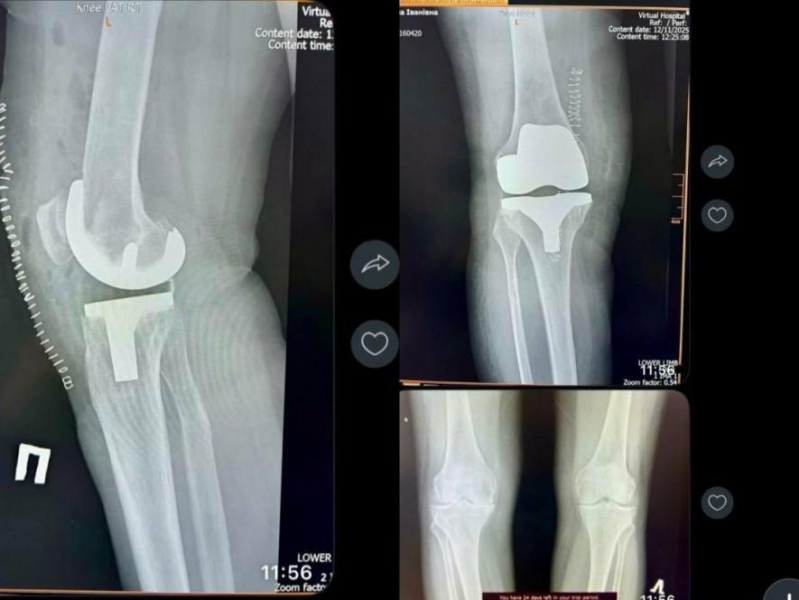

Лікарі-ортопеди-травматологи КНП “Бережанська ЦМЛ” провели тотальне цементне ендопротезування правого колінного суглоба.

Під час операції пошкоджені ділянки суглоба замінено високоточними, біосумісними компонентами ендопротеза, що відтворюють природну біомеханіку руху та забезпечують стабільність.